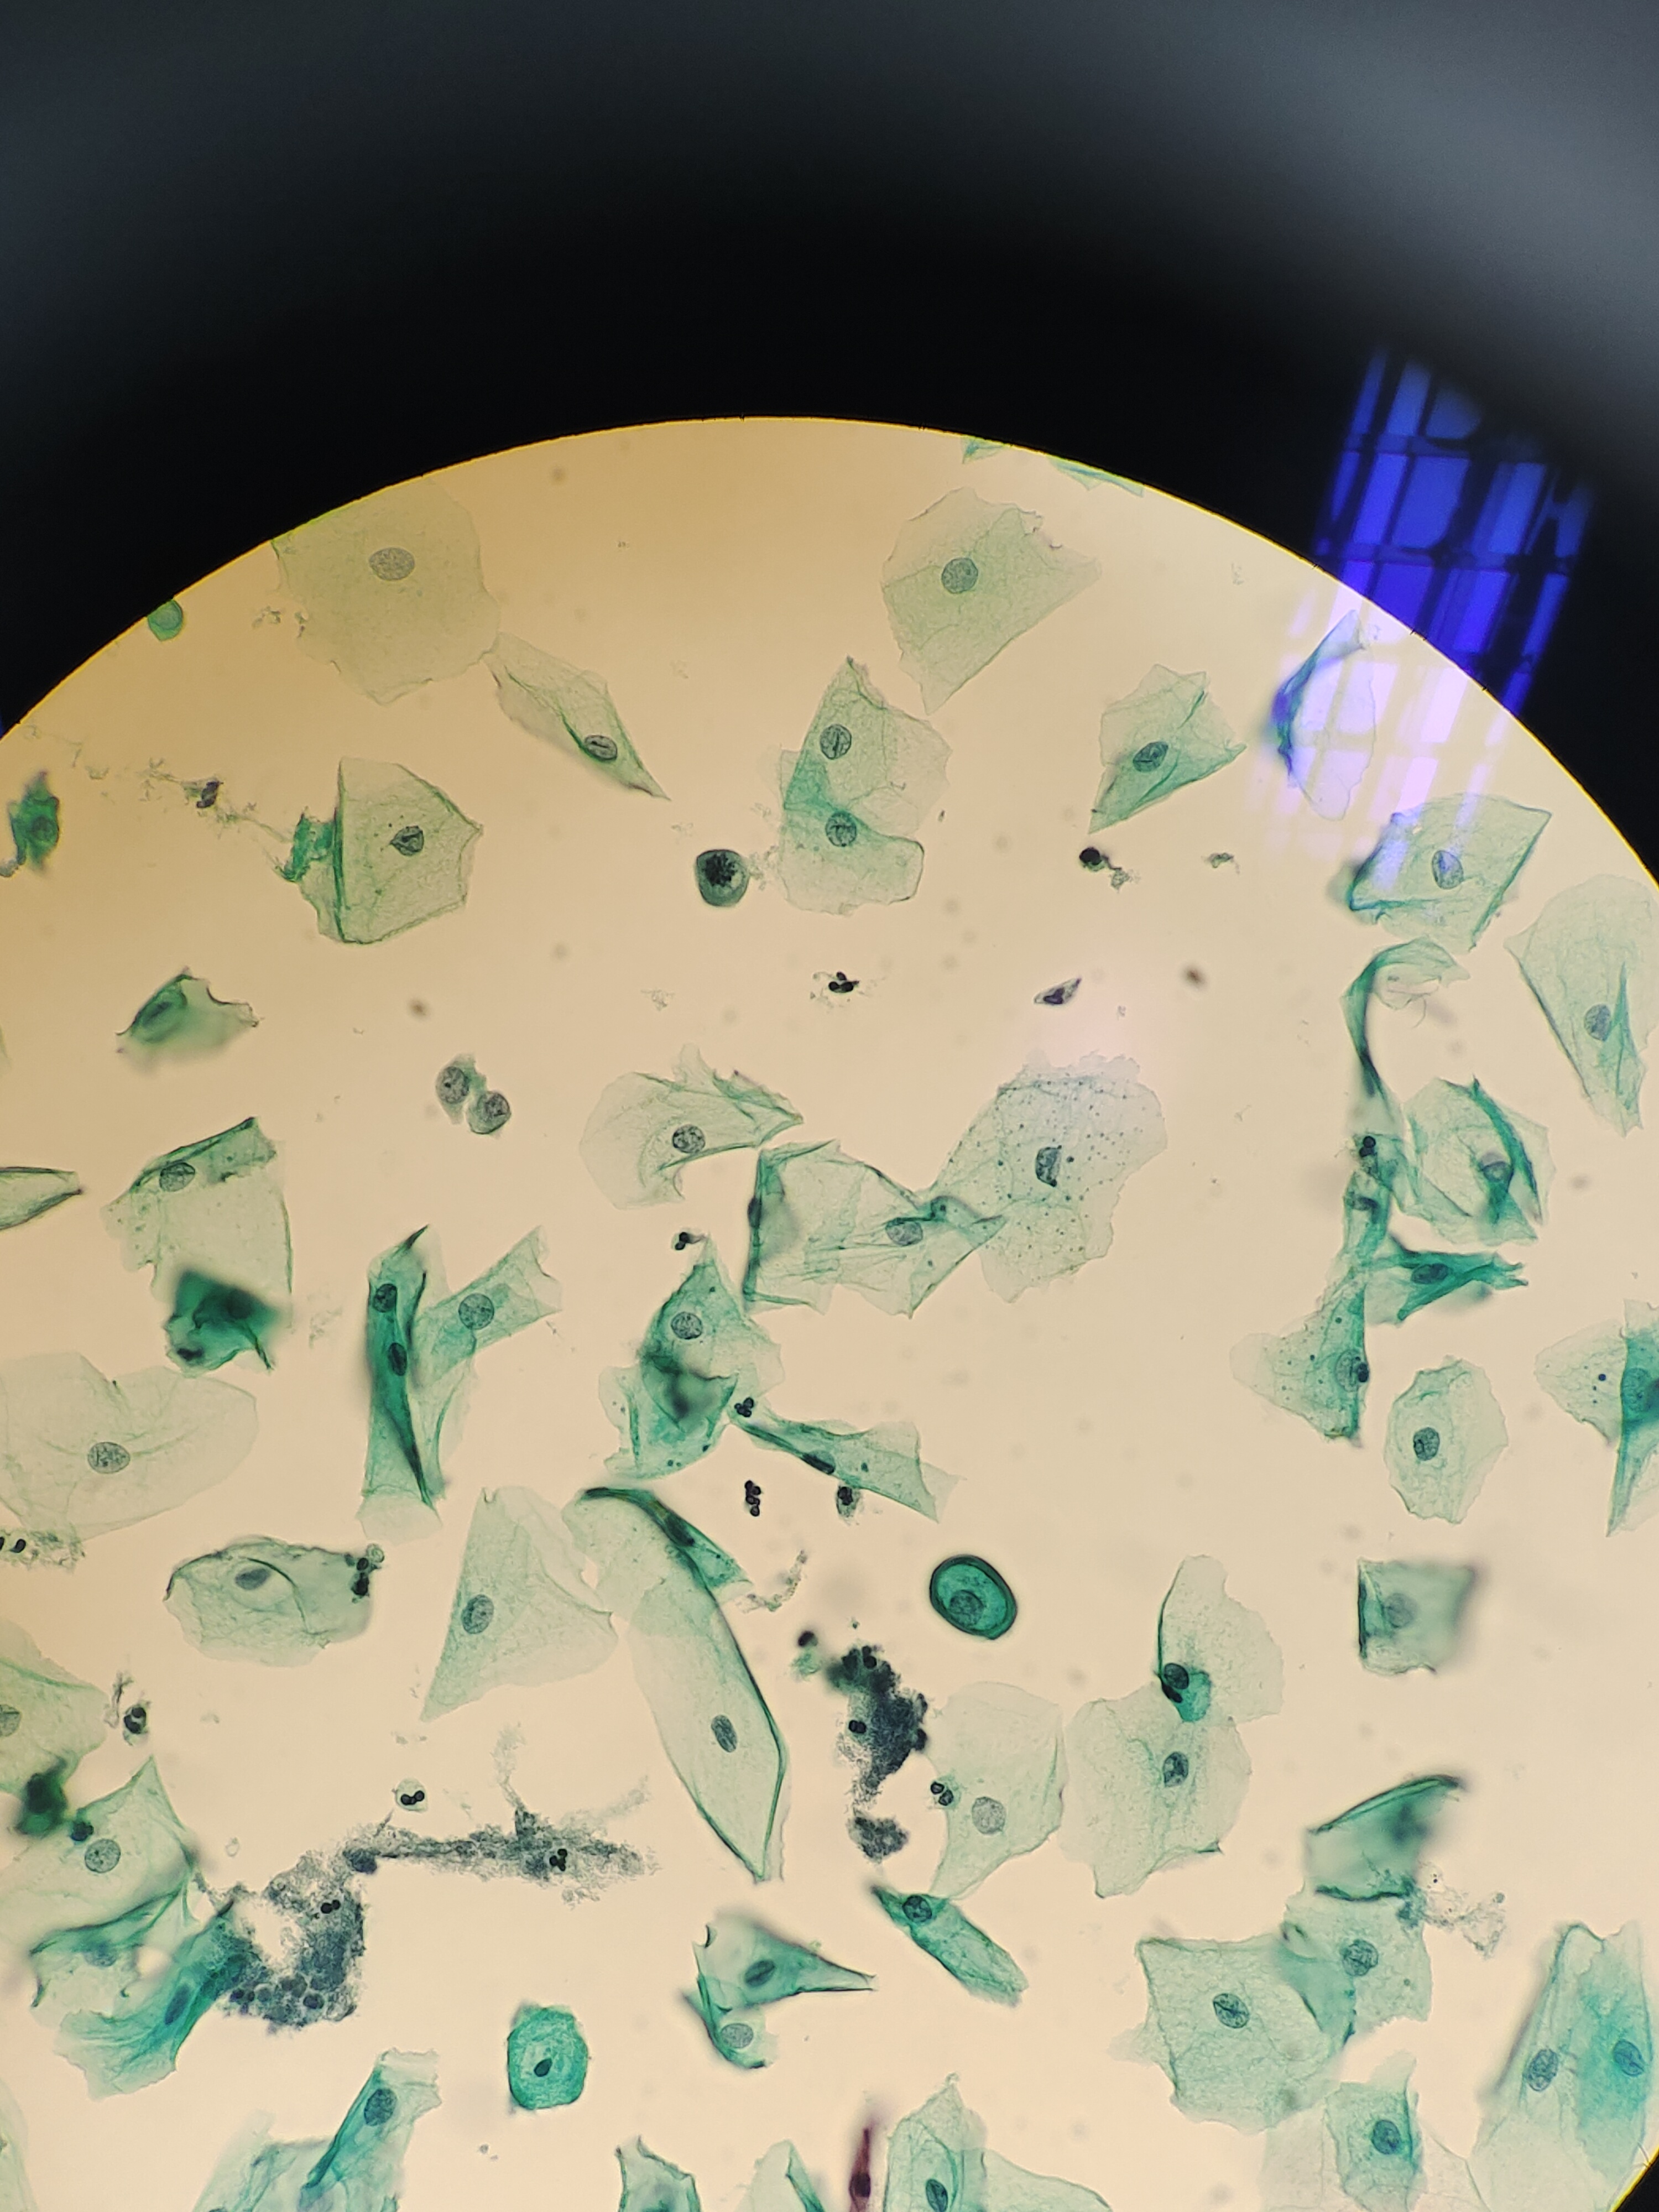

一年前曾行宫颈锥切术,术后病理不详,现复查。老师们,有些核大细胞,有事吗?

宫颈

液基

巴氏

NILM